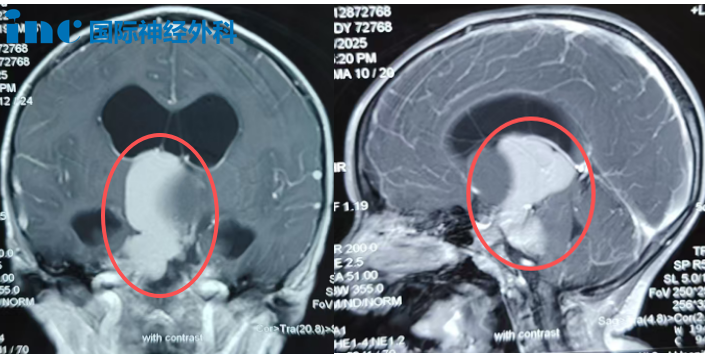

此后,伴随着搬家、换新环境,尽管小安都会有间歇性的头痛,但田先生一家也都不疑有他,直到在一次游玩途中,小安出现喷射性呕吐、头痛加剧、行走不稳等异常,一家人这才从核磁上发现了“庞然大物”——颅咽管瘤。

影像检查显示,肿瘤从鞍上延伸至第三脑室和桥小脑角区,并已引发脑积水。随着肿瘤向“生命禁区”脑干生长,小安的症状也日益加重。为了尽快手术,田先生和家人彻夜失眠,他们不放过任何一丝希望,可结果却不尽人意。